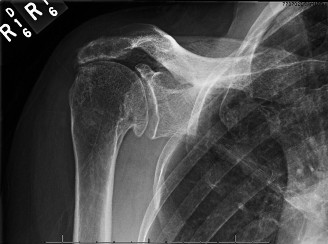

Treat a patient with infected total shoulder arthroplasty? CASE 21 A 70-year-old, right-hand-dominant female presents to clinic complaining of 4 years of gradually worsening chronic right shoulder pain and stiffness. She says the pain is worse at night and with any range of motion, denies a history of trauma, pain in other extremities, or numbness or tingling of the right upper extremity. She notes that her mother suffered from rheumatoid arthritis that affected her shoulder. Physical examination reveals decreased muscle bulk over the right supra- and infraspinatus fossae compared to the contralateral side, limited active and passive ROM, marked weakness with external rotation, and 4+/5 strength with shoulder abduction. X-rays of the right shoulder are shown in Figures 2–58 and 2–59.

Figure 2–58

Figure 2–59

The correct answer is (C). Rotator cuff tear arthropathy consists of a combination of rotator cuff insufficiency, glenohumeral joint degenerative changes, and superior humeral head migration. It is more common in women and also more often found on the dominant side. The patient’s clinical examination with weakened external

rotation and muscle atrophy signaling incompetent supra- and infraspinatus muscles point to rotator cuff insufficiency, and her plain films reveal narrowed glenohumeral joint space as well as superior migration of the humeral head. Choice D is incorrect because, while radiographs would show narrowing of the glenohumeral joint space, they would also likely show numerous osteophytes and posterior wear of the glenoid. Choice B is incorrect because, while adhesive capsulitis does present as decreased active and passive range of motion, the patient’s constellation of symptoms pointing towards rotator cuff insufficiency along with the radiographs make cuff tear arthropathy the more likely choice. Finally, Choice A is incorrect because even though she has a positive family history of rheumatoid arthritis, it is less likely to present only in a single joint. Also, rheumatoid arthritis on radiography appears more as an erosive process without the characteristic superior migration of the humeral head.